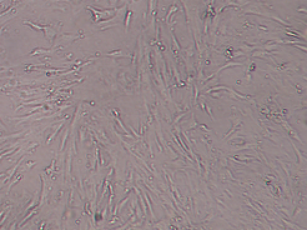

脐带间充质干细胞(P3代)

1. 细胞形态学鉴定:贴壁,成纤维细胞类似,呈梭形、不规则三角形、多边形,呈纺锤状生长,细胞中央有卵圆形核,胞质向外伸出2⁃3个长短不同的突起,当细胞密度过大时,可看到细胞成漩涡状排列。